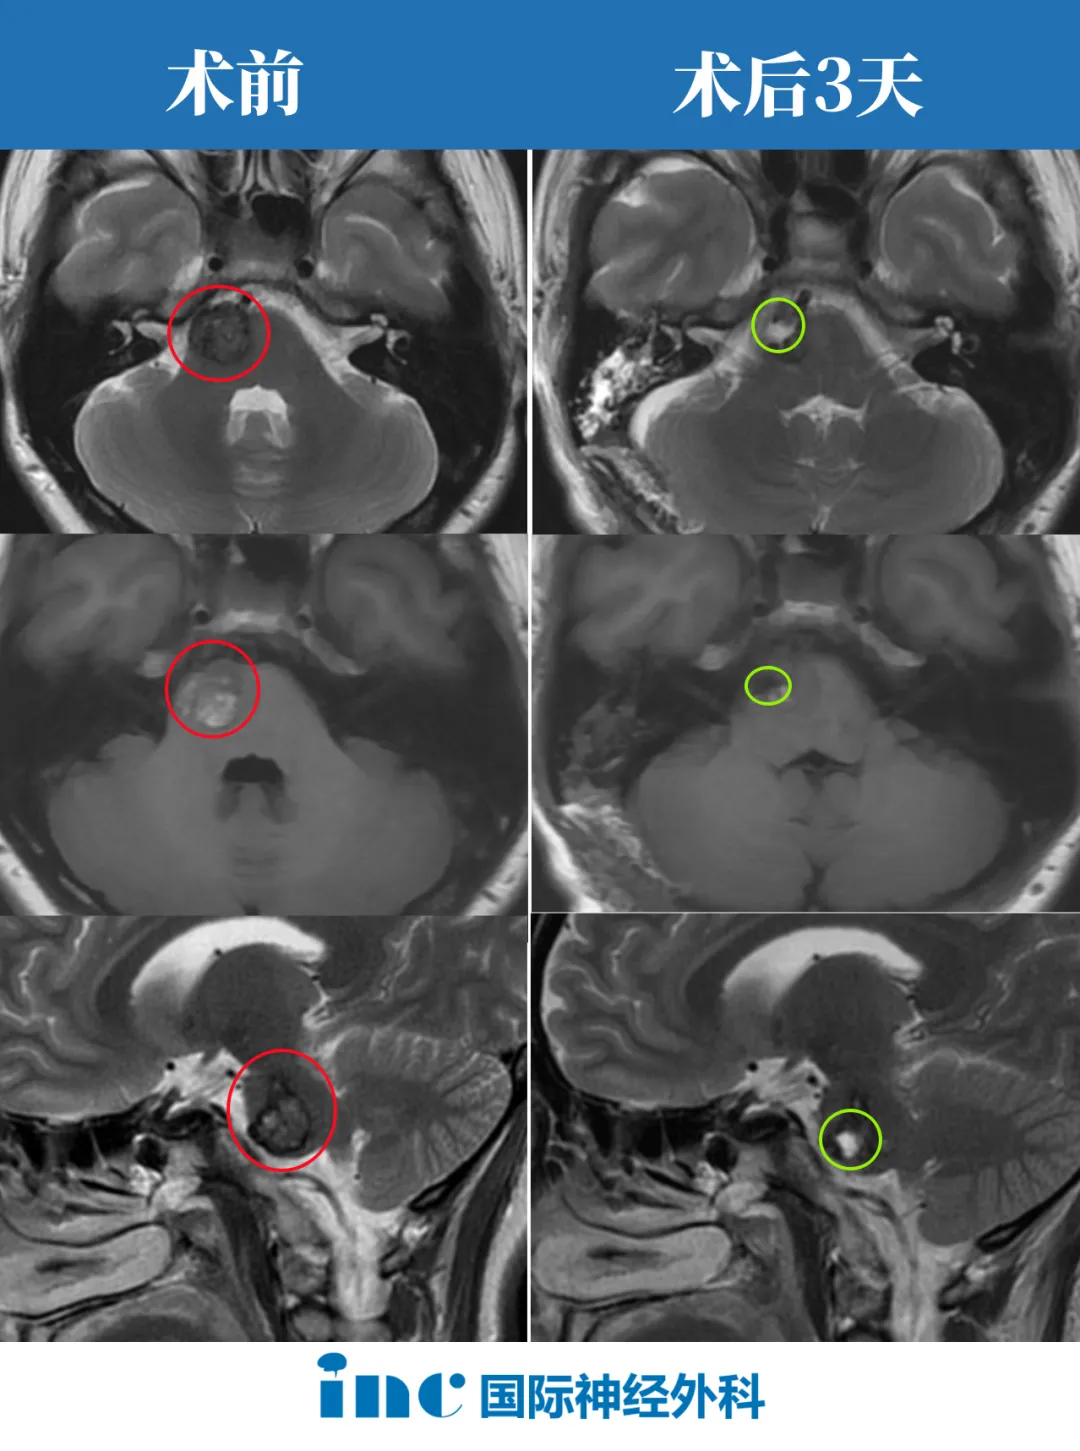

“海绵状血管瘤被切除了,所以健康的脑组织有膨胀,有点像海绵一样张开。这是正常的,海绵状血管瘤总是这样。但重要的是,它没有残瘤。”

2023年巴教授9月中国行期间,一场疑难脑瘤示范手术成功拯救了年轻的佩珊于病魔的阴影之中。经INC巴教授成功手术后,不仅得到了全切,且较害怕的偏瘫、面瘫等也没有发生,也不需要后续放疗辅助,在ICU待了一天就出来了。这个结果对37岁的脑干海绵状血管瘤患者佩珊来说也是幸运之神降临。

术后3天,巴教授查房时,佩珊看到前来问候查房的巴教授时,手舞足蹈、开心比心。兴奋的她激动得对巴教授“表白”感谢:“巴教授您太帅了,I Love you!巴教授也跟佩珊开心得比心。她的治疗路上充满挣扎和痛苦,但更多的却是驱散黑暗的明媚阳光。

佩珊:现在我觉得很好、很好,四肢完全正常。就感觉有点胀胀的,其他都没事,完全没问题。听力也很好,眼睛、复视什么都没有,走路那些也挺好的。我昨天都走路了。感到很开心,幸运了,完全没问题,我真的是我刚睡醒我就摸一下脸有没有看面瘫,手脚都是用都没事,就觉得好幸运。真的感谢巴教授,很厉害的,真的救了我们,救了大家。